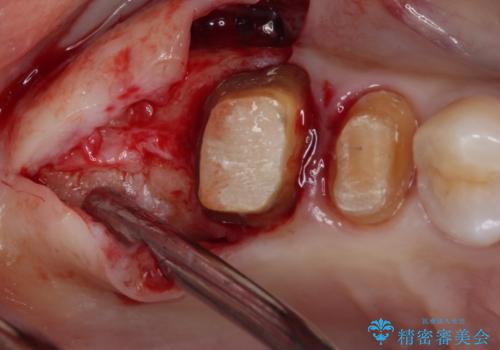

不安定な咬み合わせとなっており、クラウンの表面が剥離していたため、インプラントによる欠損補綴治療を行い、手前2つの歯も一緒に補綴治療を行うこととしました。

治療中の仮歯も頻繁に壊れておりましたが、インプラントの土台が歯肉上に出てからは咬み合わせが安定し、仮歯が壊れることもなくなりました。